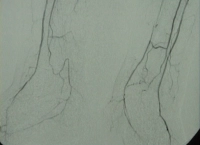

DAOP perna direita grau IV de Fontaine, perna esquerda grau III com:

- Arteriosclerose de alto grau da aorta terminal e de ambas as artérias ilíacas

- Oclusão estendida de ambas as artérias femorais superficiais

- Oclusão parcial das artérias infrapoplíteas em ambas as pernas

DSA pré-operatória: